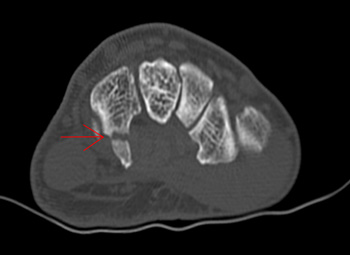

Figure 4. Hook of hamate fracture visualized through CT scan

Courtesy of the San Diego Climbing Community

Acute traumatic injuries can occur from falls (e.g., falling on an outstretched hand), sudden slips while gripping holds, or violent dynamic moves. Falls or impacts can lead to fractures or dislocations. For example, a sudden slip from a Sloper grip (Figure 1B) can result in hamate hook fracture, thumb medial collateral ligament (MCL) injury, or finger pulley injury. Unlike injury in contact sports, in which a hamate fracture may be due to a direct blow, hook of hamate fractures are reported among climbers using undercling holds or other forceful grip techniques. Injury presents as ulnar-sided palm pain and can be missed on standard radiographs (Figure 4). Nondisplaced fractures heal with immobilization, but persistent symptoms or displacement often warrant surgical treatment of the fracture. Surgical excision may result in finger flexion weakness and should be avoided in this population when possible. Triangular fibrocartilage complex (TFCC) tears are an additional cause of ulnar-sided pain; they are seen with an increased incidence in climbers and may be confirmed through MRI imaging. Another common type of acute trauma injury occurs as a collateral ligament injury to the thumb metacarpophalangeal (MP) joint or long finger PIP joint. Surgical indications for long finger PIP collateral ligament injuries are not well defined.